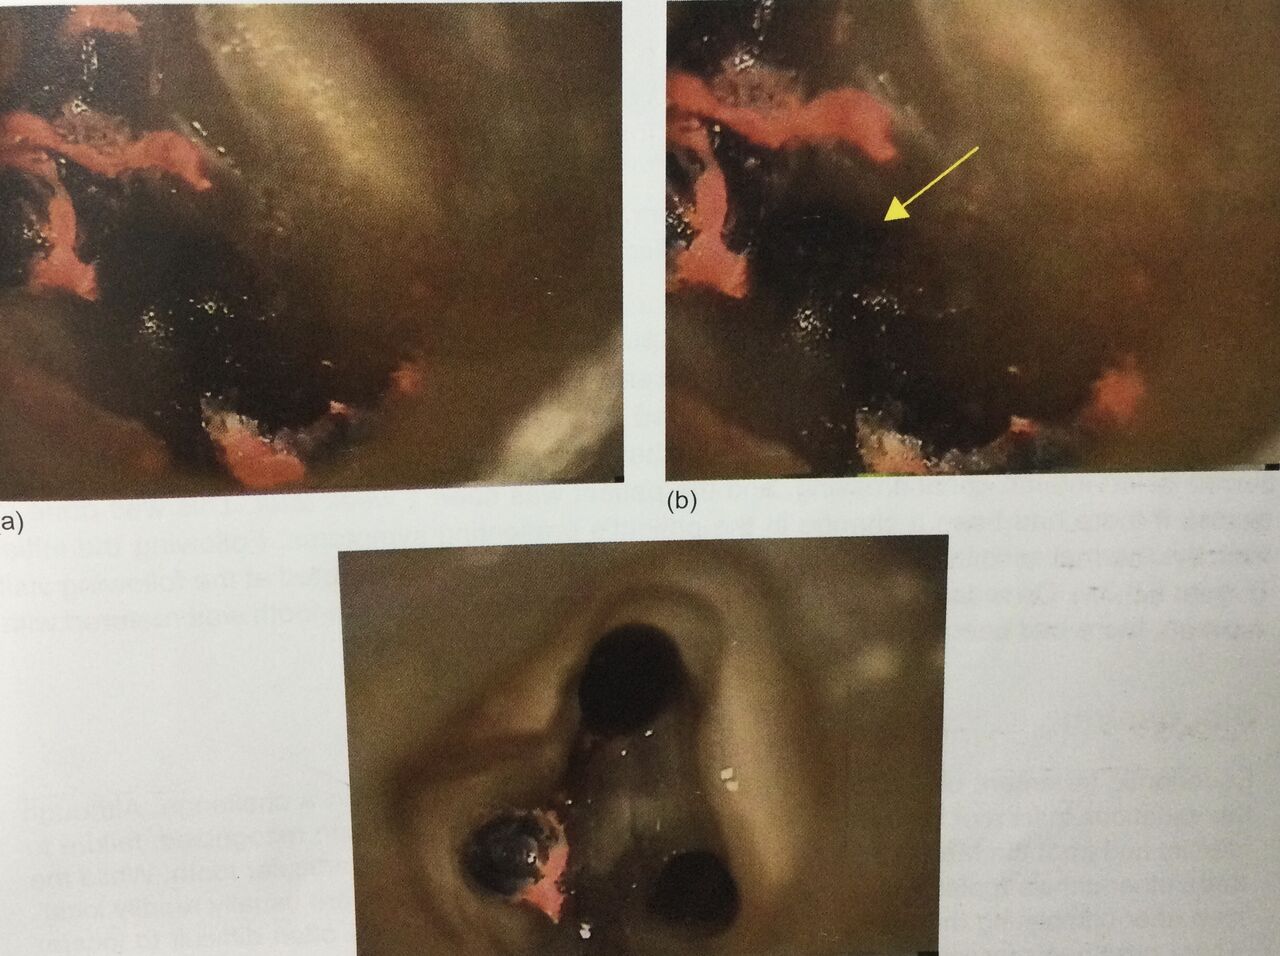

麻酔をして、ラバーダムをかけてプラスチックを外しました。

顕微鏡で大きくして神経の部屋の床部分を観察します。

前に詰めてある神経の管から伸びるスジ状の神経が見つかりました。

四つ目の神経ですよね。

左上の絵が最初で、オレンジ色のが前に詰めてあるガッタパーチャのゴム。

入り口を削っちゃってありますが、3つあるでしょう。

右の絵の矢印が4番目の見逃された神経です。

で、そこを削って広げたのが、下の絵です。

顕微鏡で大きくして、

そこにあるはずだ!って意識を持って探さないと見つかりません!